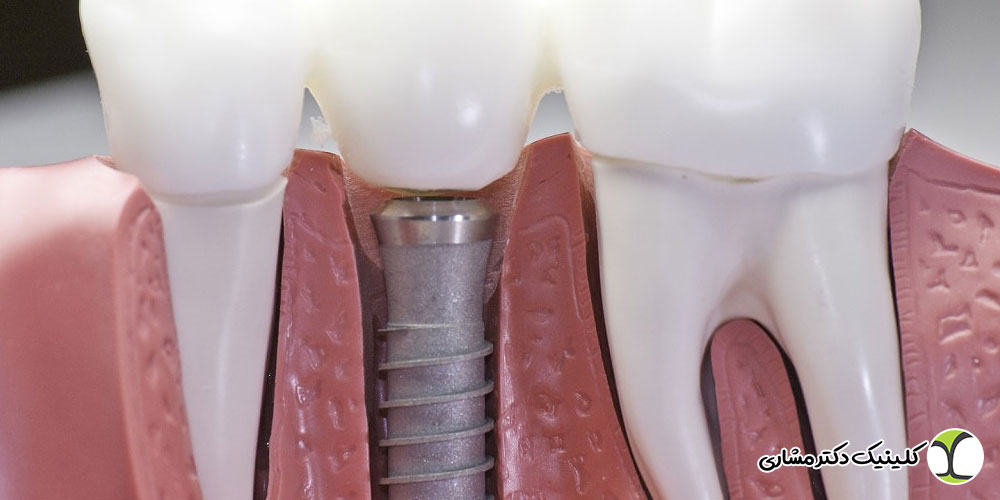

ایمپلنت دندان یکی از بهترین راه ها برای جایگزین کردن دندان های از دست رفته است که اگر بعد از انجام آن به خوبی از آن مراقبت شود، می تواند سال ها بدون مشکل باقی بماند و مثل یک دندان طبیعی کار کند. اما فقط گذاشتن ایمپلنت کافی نیست و برای اینکه عمر آن بیشتر شود، لازم است بعد از انجام ایمپلنت، مراقبت هایی را به درستی انجام دهید. رعایت این نکات ساده کمک می کند ایمپلنت شما سالم بماند و دچار مشکل نشود.

اگر می خواهید بعد از ایمپلنت، دندان جدیدتان عمر طولانی داشته باشد و به خوبی در استخوان فک جا بیفتد، باید از همان روز اول با دقت از آن مراقبت کنید. مراقبت های بعد از جراحی، کمک می کنند زخم ها زودتر خوب شوند و خطر عفونت یا آسیب به ایمپلنت کمتر شود. در ادامه، برخی از نکات مهم که برای مراقبت در روزهای اول بعد از کاشت ایمپلنت باید رعایت شود را بررسی می کنیم:

برای اینکه ایمپلنت دندان عمر طولانی تری داشته باشد و دچار مشکل نشود، فقط مراقبت های خانگی کافی نیست. خیلی مهم است که بعد از انجام ایمپلنت، به یک دندانپزشک متخصص و باتجربه مراجعه کنید تا وضعیت ایمپلنت شما به طور منظم بررسی شود. دکتر امیرعباس مشاری، متخصص درمان ریشه (اندودونتیست)، با سابقه ویژه در تهران، یکی از بهترین گزینه ها برای این کار هستند. ایشان با دقت وضعیت لثه، استخوان فک و سلامت عمومی دهان شما را بررسی می کنند و با ارائه راهکارهای مناسب، کمک می کنند ایمپلنت شما سالم بماند و سال ها بدون مشکل کار کند. اگر می خواهید مشاوره یا نوبت ویزیت بگیرید، می توانید از طریق شماره های درج شده با مطب دکتر مشاری تماس بگیرید یا از طریق سایت ایشان، نوبت خود را رزرو کنید.